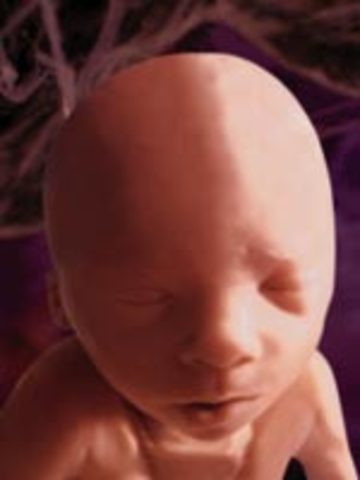

• Week 12

Week 12

Fetus' face is starting to look like a human baby. Nails start appearing. Pancreas begins to function and fetus can hiccup and suck thumb

• Week 13

Week 13

First Trimester ends. Baby starts to replace carto;age and ribs start forming and being visible. Baby starts moving more noticable.